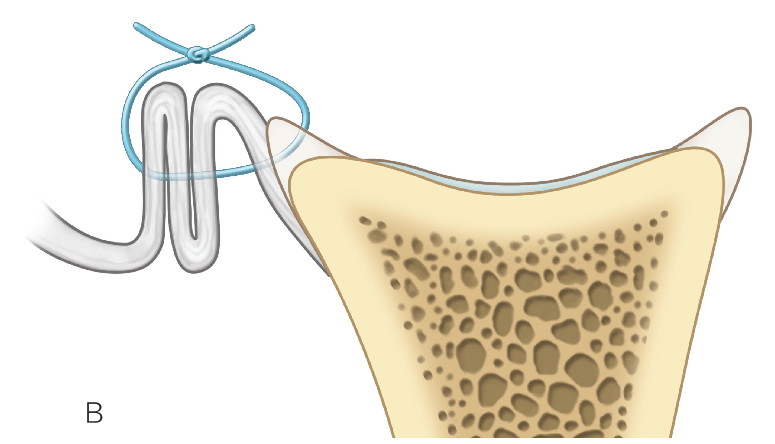

上盂唇修复

创建前方和后方入路时,与关节盂面成恰当角度,以便锚钉的置入。 高位和外侧放置前方入路可以有效地进行单纯上盂唇的修复。该入路位于肩袖间隙的高位和外侧,用腰椎穿刺针进行定位。非刚性套管有助于在肱二头肌腱附着部后方置入锚钉。 可用于 SLAP 修复的辅助入路包括 Wilmington 入路(肩峰后外侧角前方、外侧各 1 cm 处)或 Neviaser 入路(锁骨、肩峰、肩胛冈组成的三角形内,肩峰内侧 1 cm 处)。

B. 应首先用腰椎穿刺针确定辅助入路的恰当位置和方向。然后在皮肤上做一个小切 A B 口,钻头导向器置入关节。